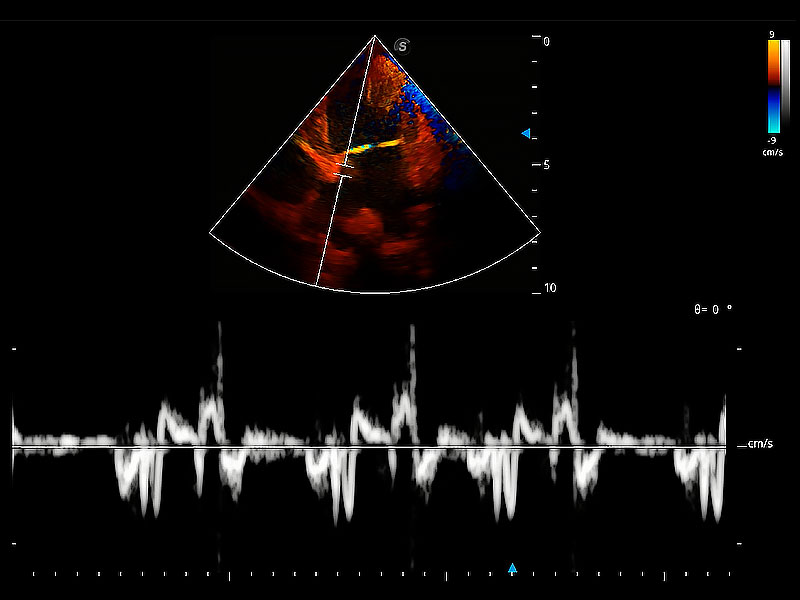

實(shí)時用顏色表示心肌組織運(yùn)動,觀察和定量組織的運(yùn)動情況,對快速檢測與評估心肌的灌注和活性、電傳導(dǎo)及心肌收縮和舒張功能等均能提供重要的診斷信息。